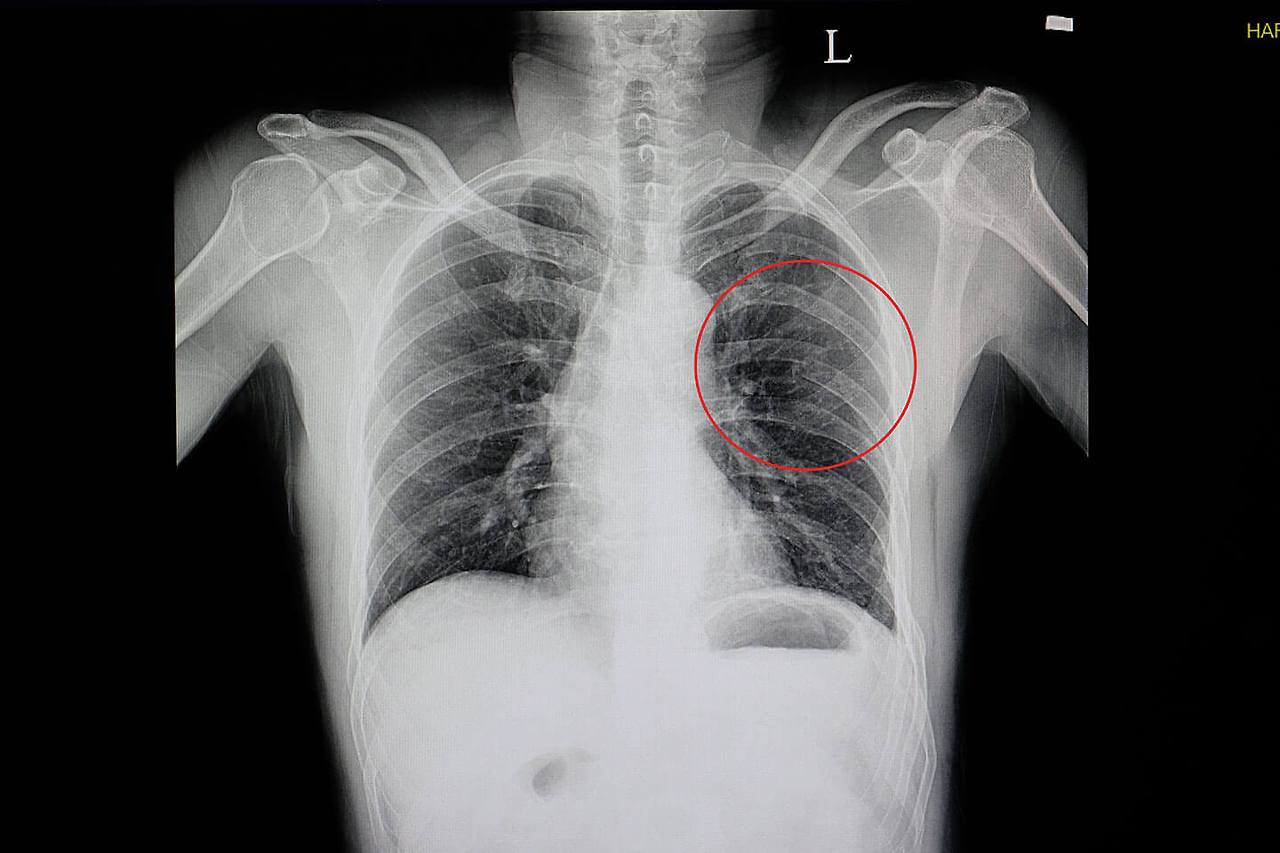

갈비뼈 금간 증상이 있다고 해서 모두 CT를 찍는 것은 아닙니다. 진료에서는 손상 경위, 통증 위치, 압통 유무, 호흡 상태, 산소포화도, 흉부 청진 등을 먼저 확인합니다. 단순 골절 의심이며 호흡 상태가 안정적이면 엑스레이 없이 보존적 치료를 시작하는 경우도 있습니다. 반면 외상이 크거나, 숨이 차거나, 폐 손상이 의심되거나, 다발성 골절 가능성이 있으면 영상검사가 더 적극적으로 진행될 수 있습니다. 즉, 검사 여부는 “뼈가 정말 금이 갔는지”만 확인하기 위한 목적보다, 위험한 합병증이 숨어 있는지를 판단하기 위해 결정되는 경우가 많습니다.